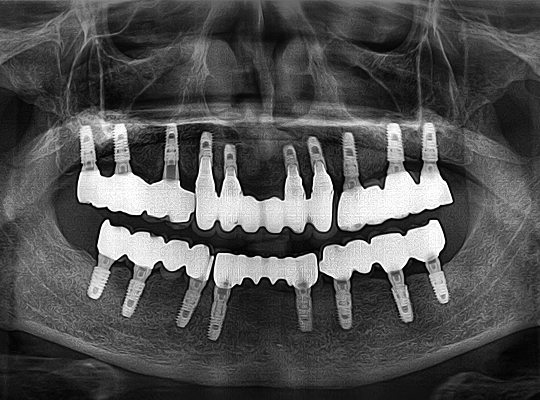

• 자체 기술로 제작한 치아몸통을 연결하여

임플란트를 4~6개만 식립 가능

식립 개수를 줄이는

시니올 임플란트

식립 개수가 많은 과거의 임플란트

식립 개수를 줄인 시니올 임플란트

과거에는 대교 건설 시 기술이 부족해 교각을

촘촘히 세웠지만,

현대에서는 공법이 발달해

교각 수를 줄일 수 있게 되었습니다.

임플란트도 마찬가지 입니다.

컴퓨터 분석과 젊어지는치과의

21년의 전체 임플란트

노하우를 통해

식립 개수를 줄이면서도 완성도를

높일 수 있게 되었습니다.